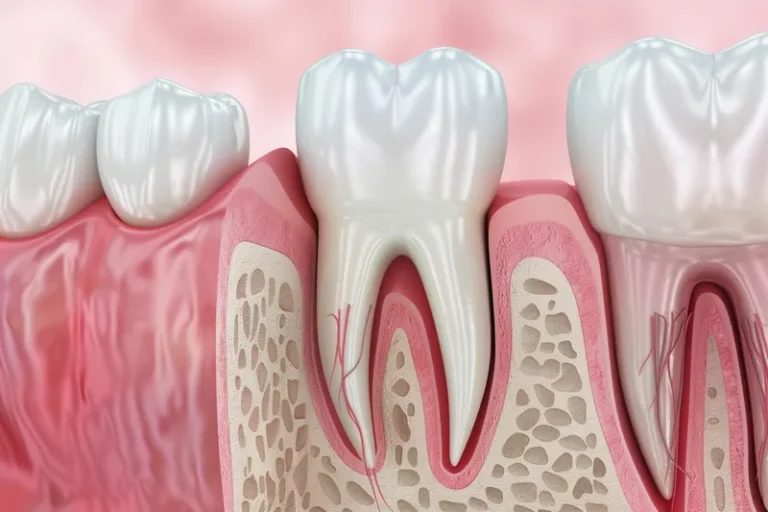

La osteointegración es el proceso biológico fundamental que determina el éxito de los implantes dentales. Durante este fenómeno, el hueso del maxilar crece y se fusiona directamente con la superficie del implante de titanio, creando una conexión estructural y funcional que garantiza la estabilidad a largo plazo. Este proceso, descubierto por el profesor Per-Ingvar Brånemark…

La sanación de un implante dental es un proceso gradual que varía según cada paciente. Generalmente, la integración completa del implante con el hueso (osteointegración) tarda entre 3 y 6 meses, aunque la recuperación inicial de los tejidos blandos ocurre en las primeras semanas. Durante este período, es fundamental seguir las indicaciones del especialista para…